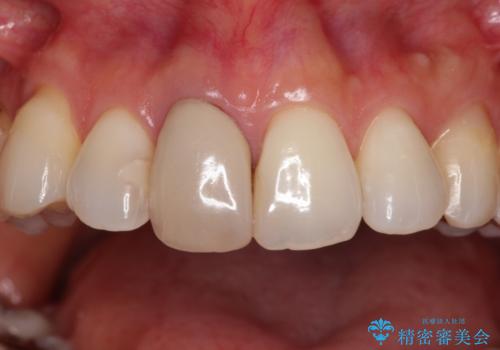

失活により変色した前歯 オールセラミッククラウンによる審美歯科治療

- 前歯の変色を気にして来院された患者様です。

ラミネートベニアによる治療を以前受けていたものの、神経組織が失活して以降、徐々に変色してきたとのことでした。

オールセラミッククラウンにて補綴治療を行うこととしました。

周りの歯と調和した、自然な仕上がりとなりました。